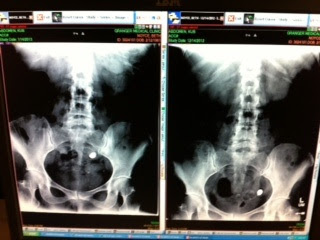

Here's an iphone photo I took of the image on the radiology tech's computer screen. The image on the right is the X-ray I had at Granger Medical Center in December. The image on the left is the X-ray done at the same clinic on Monday, January 14, two days ago.

It looks like it's retreated to a higher position. "Geographically," that's true. But remember that the small bowel loops around and up and down countless times in the abdomen. And peristalsis (the bowel’s normal contraction-and-release cycle) does not usually move bowel contents back toward the stomach, but rather toward expulsion.

Anatomically, the capsule is now probably lower than, or distal to its position before the double-balloon enteroscopy, during which the higher, or proximal stricture was dilated.